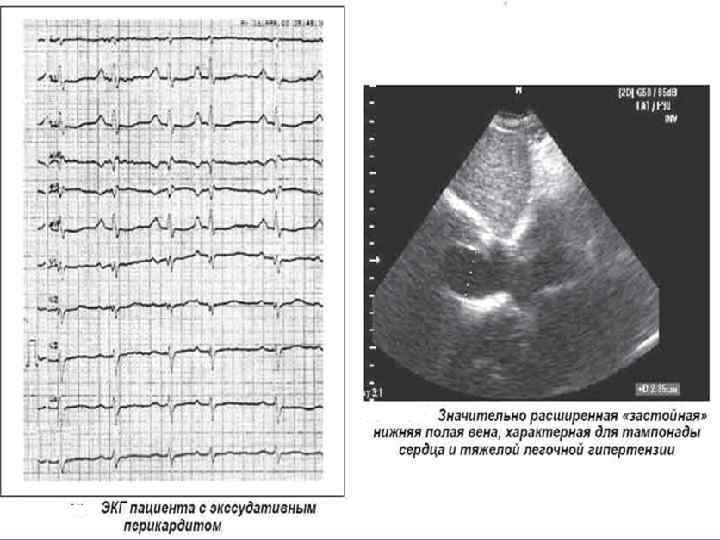

ЭКГ при выпотном перикардите • Характерным ЭКГ признаком выпотного перикардита является низкий вольтаж комплекса QRS во всех отведениях, который обусловлен затуханием электрического сигнала при прохождении его через слой жидкости в полости перикарда. • Воспалительные изменения субэпикардиального слоя миокарда вызывают незначительный подъем сегмента ST от изолинии и генерализованную инверсию зубца T, так же, как и при сухом перикардите. • Реже возникают аритмии, признаки перегрузки предсердий, увеличение интервала PR.

Инструментальные данные тампонады сердца: • ЭКГ – признаки: уменьшение амплитуды зубцов, высокие остроконечные зубцы Т в грудных отведениях либо картина, свойственная выпотным перикардитам • ЭХОКС: накопление жидкости в перикарде, наличие диастолического коллапса правого предсердия и правого желудочка; наличие дилатации нижней полой вены; • Рентгеновское исследование грудной клетки: cor «бутылка воды» , увеличение размеров сердца, сглаженность сердечных дуг, уменьшение амплитуды пульсации или полное ее исчезновение. • КТ сердца для выявления поражения перикарда

• При начинающейся тампонаде сердца увеличение давления в полости перикарда препятствует наполнению правого желудочка и, следовательно, нормальному коллабированию нижней полой вены. • Это первый признак развивающейся тампонады сердца: недостаточное коллабирование нижней полой вены появляется еще до спадения правых отделов сердца на выдохе.

• Коллабирование нижней полой вены после глубокого вдоха составляет менее 50%. • Имеется сильная связь между давлением в правом предсердии и поведением нижней полой вены. • При коллабировании ее менее, чем на 50%, указывает на то, что давление в правом предсердии превышает 10 мм рт. ст. ,